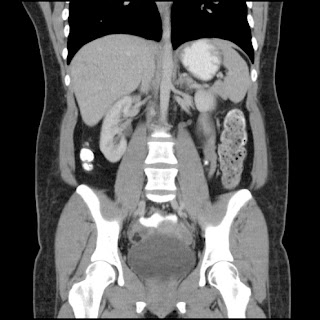

Mujer de 57 años.

Cuadro clínico de 1 mes de evolución caracterizado por distensión abdominal e hiporexia.